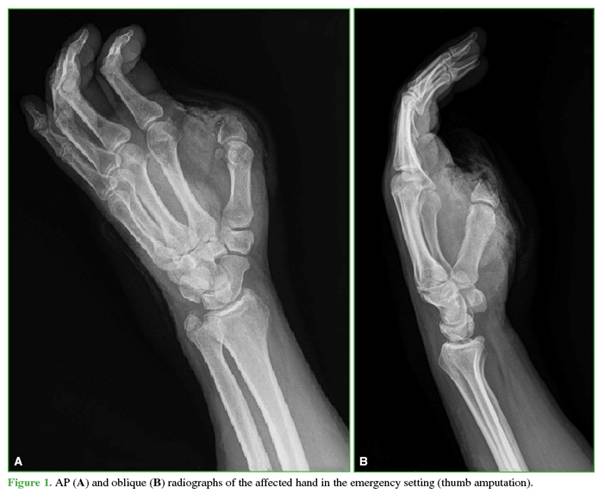

A 58-year-old male pharmacist presented with a traumatic amputation of the thumb at the metacarpophalangeal level, with a failed replantation attempt, in his dominant hand. Because he declined reconstruction using a toe-to-hand transfer, osteoplastic reconstruction was proposed (Figure 1).